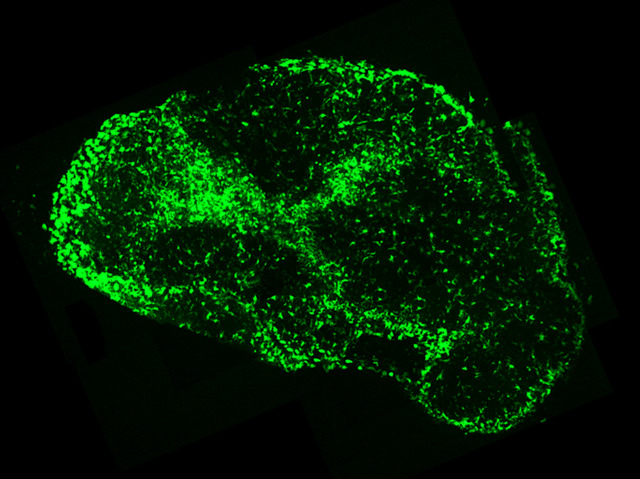

Most people who catch a dose of the food poisoning bacteria Salmonella just suffer a nasty bout of diarrhoea. But if the bacteria spread through the body, which can occasionally happen in young children and the elderly, this 'tummy bug' can be life-threatening. Treatment with antibiotics often works, but sometimes the infection comes back with a vengeance when the drugs stop. To discover why, researchers are studying mice that suffer from Salmonella infections in the same way we do. They've found that the bacteria 'hide out' in special immune cells called dendritic cells – highlighted green in this image of an infected mouse's lymph node – and slow down their growth. This enables them to lay low and resist antibiotic treatment, so they can grow again afterwards. Stimulating the immune system helps to flush out these sneaky bugs, which could be a new approach for treating severe infections in future.